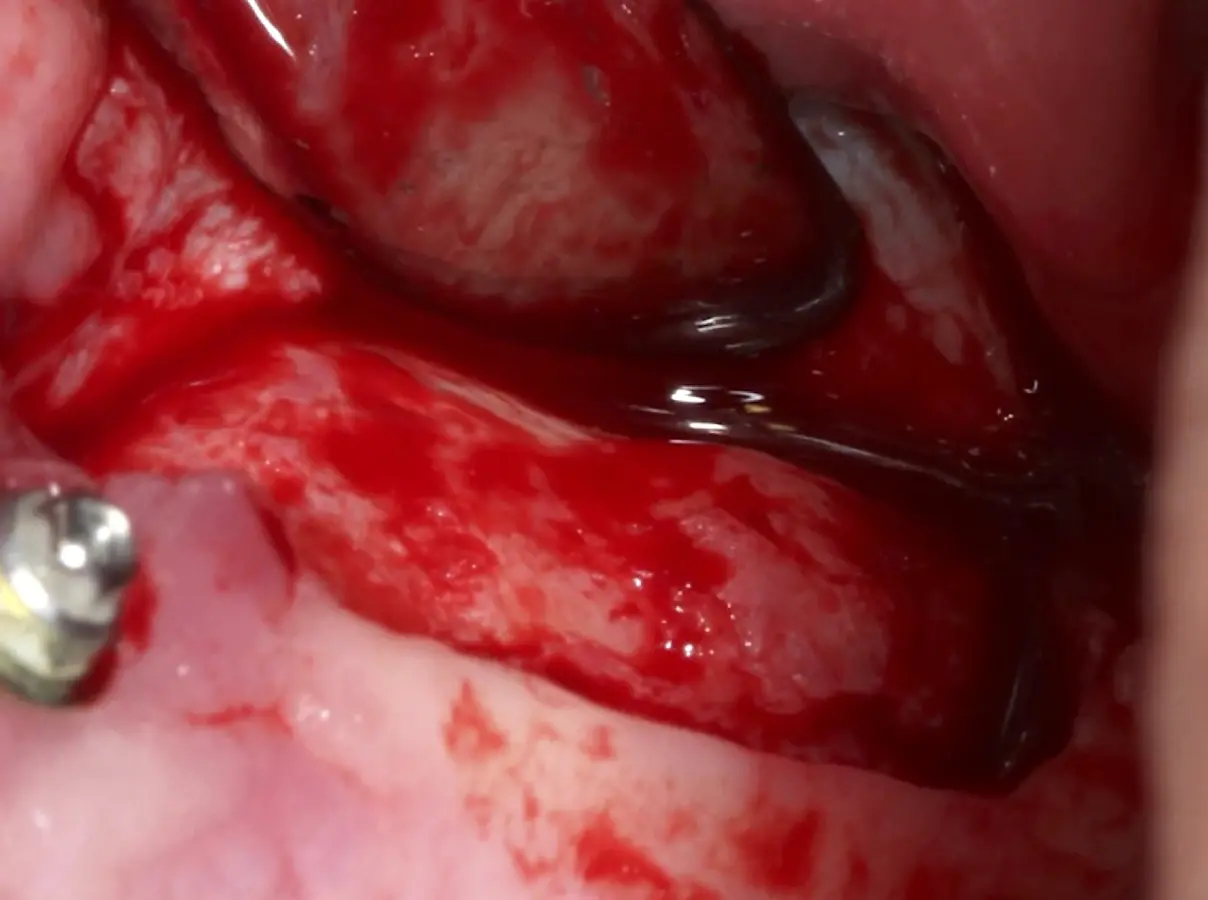

Figura 17. Inicio del desprendimiento de la membrana de Schneider con el inserto de presión hidráulica.

Figura 18. Elevación de la membrana de Schneider con curetas manuales (a, b).

Figura 25. Introducción del bloque óseo de la pared lateral dentro del seno maxilar: inicio del desprendimiento de la membrana con el inserto de presión hidráulica.

Figura 26. Decolado de la membrana de Schneider hasta la pared medial del seno maxilar (a). Desplazamiento de la pared ósea lateral al interior del seno maxilar transformándose en parte del techo de la ventana o nuevo piso del seno (b).